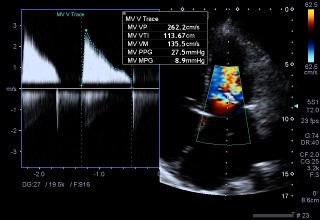

Ecocardiograma

O ecocardiograma é um exame médico não invasivo que utiliza ultrassom para criar imagens detalhadas do coração. Ele fornece informações sobre a estrutura, função e fluxo sanguíneo do coração, sendo essencial no diagnóstico e monitoramento de diversas condições cardíacas, como doenças das válvulas, insuficiência cardíaca e anomalias congênitas.

Durante um ecocardiograma, o paciente geralmente deita-se em uma mesa enquanto um técnico ou médico aplica um gel condutor na pele do peito. Em seguida, um transdutor de ultrassom é movido suavemente sobre a região do coração, emitindo ondas sonoras que são refletidas pelos tecidos do coração. Um computador converte essas ondas sonoras em imagens em tempo real, que mostram as câmaras, válvulas e estruturas do coração em detalhes.